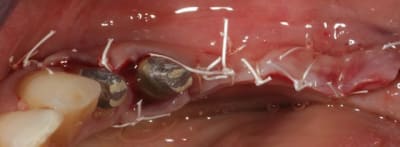

Cas 1-coté gauche maintenant:

photo:

1- ouverture, forme et configuration différente

2- une fois échauffée avec le coté droit, je me dis allez hop, j'attaque une expansion. donc incision crestale avec décharges osseuses

3- mise en place des expanseurs de Mesinger A et B

4-5 notez que l'incision de décharge étant oblique , elle sert également de garde fou contre une éventuelle fracture osseuse. l'os "mobile" vient buter contre l'os "immobile"

la suite en primeur pour ceux qui viennent à Sallanches les 28 et 29 Mars...